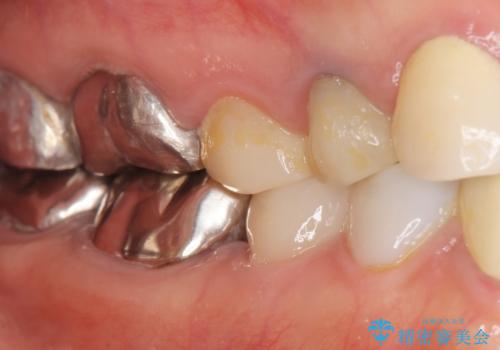

被せ物を入れたばかりの歯が痛む 40代女性

精査したところ、被せ物を入れたばかりの右下の小臼歯(右下5)は不可逆性歯髄炎により神経をとる処置(抜髄)が必要な状態でした。

根管治療後、セラミッククラウンによる補綴治療を行いました。

クラウンの種類:オールセラミッククラウン エコノミー